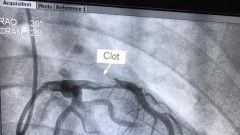

บุหรี่ต้องเลิกสูบนะค่ะ‼️ ไม่งั้นจะเป็นแบบนี้‼️